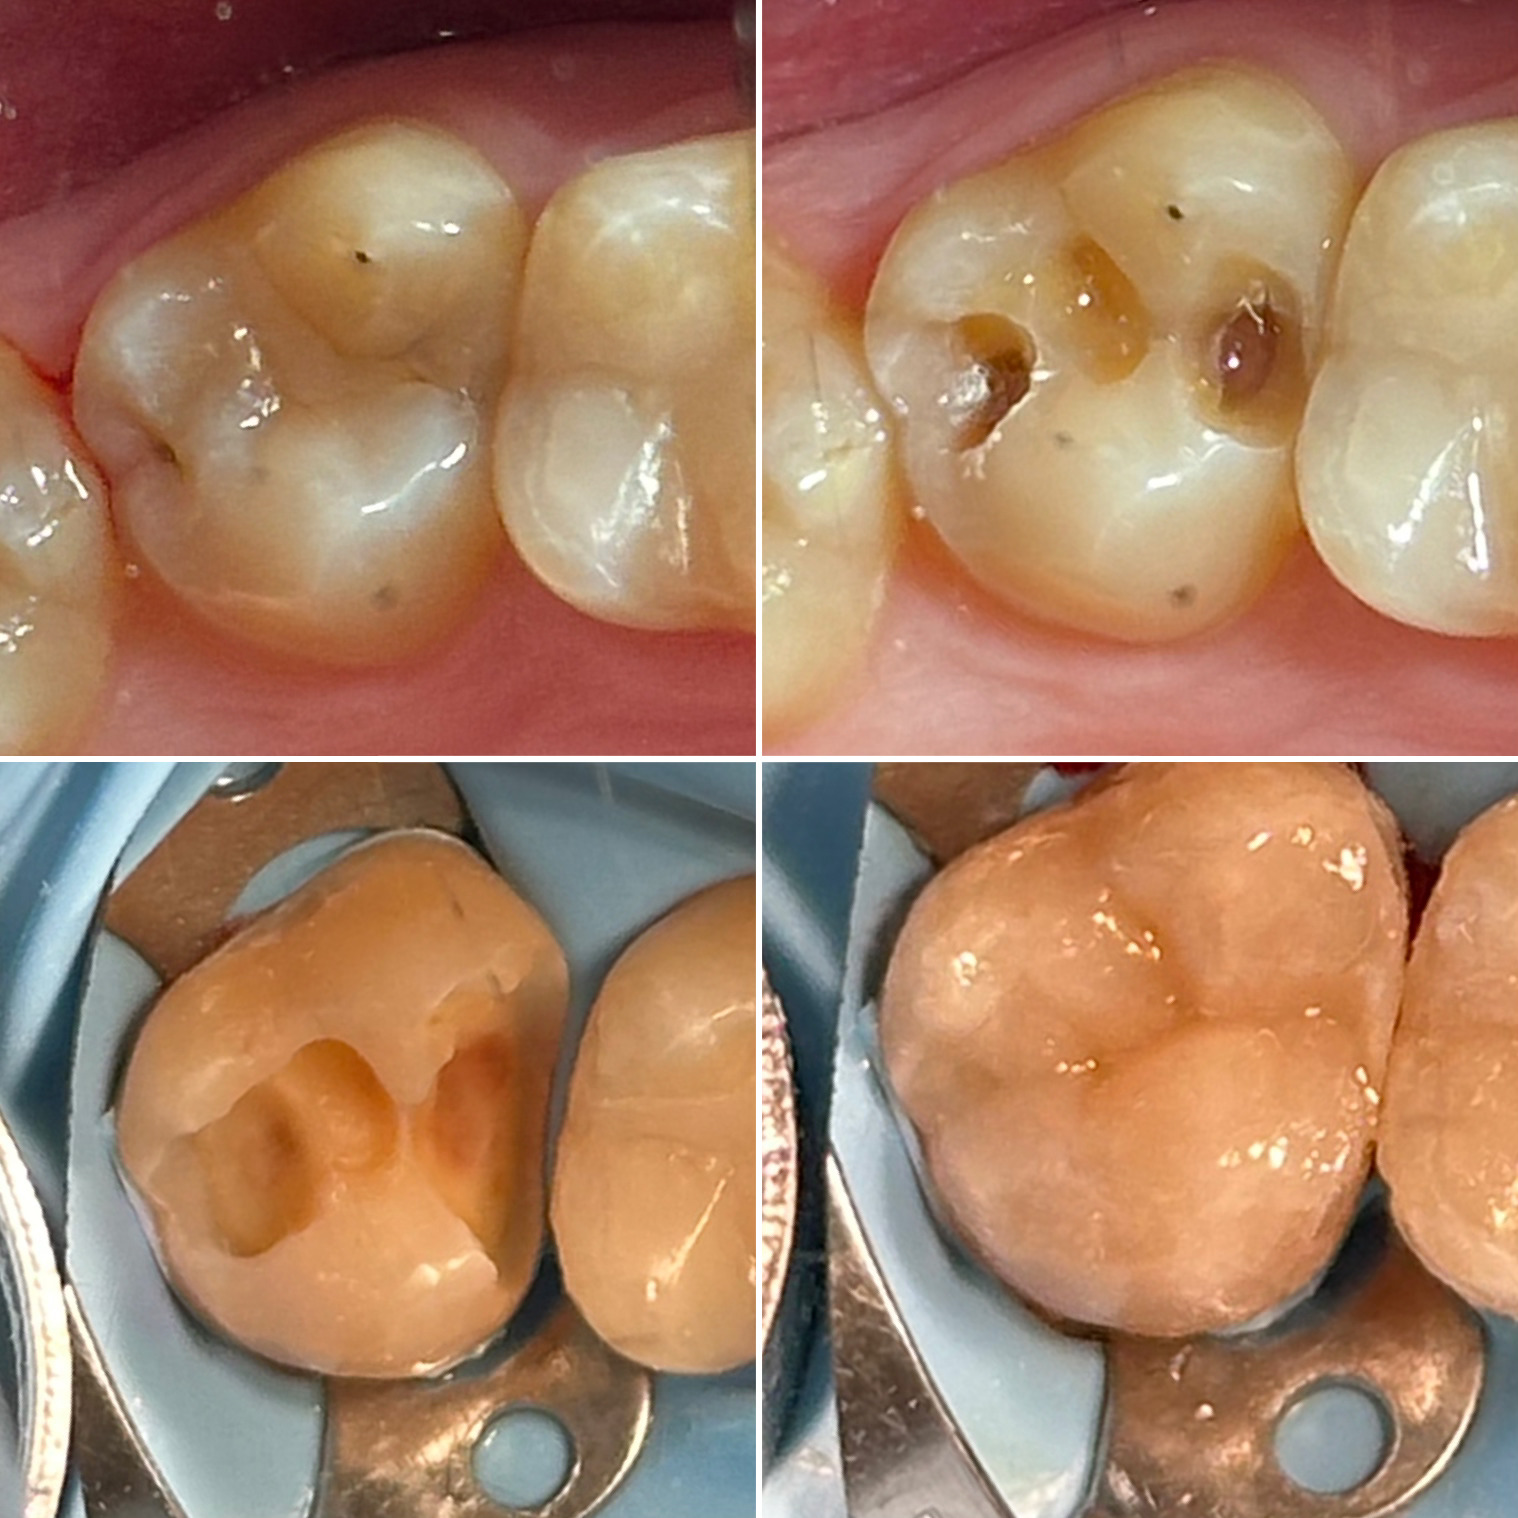

• Диагностика и лечение кариеса и его осложнений (пульпиты, периодонтиты)

• Эндодонтическое лечение корневых каналов с использованием стоматологического микроскопа

• Художественная реставрация фронтального и бокового участка зубов